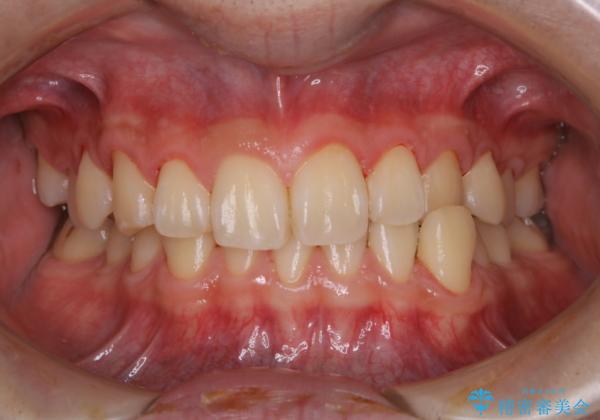

人生で初めてのクリーニングということもあり、プラークや歯石が大量に付いていました。それにより、歯茎の腫れもあり出血も多かったです。これから矯正をスタートしていくため、歯ブラシ指導を行いホームケアを頑張ってもらっています。